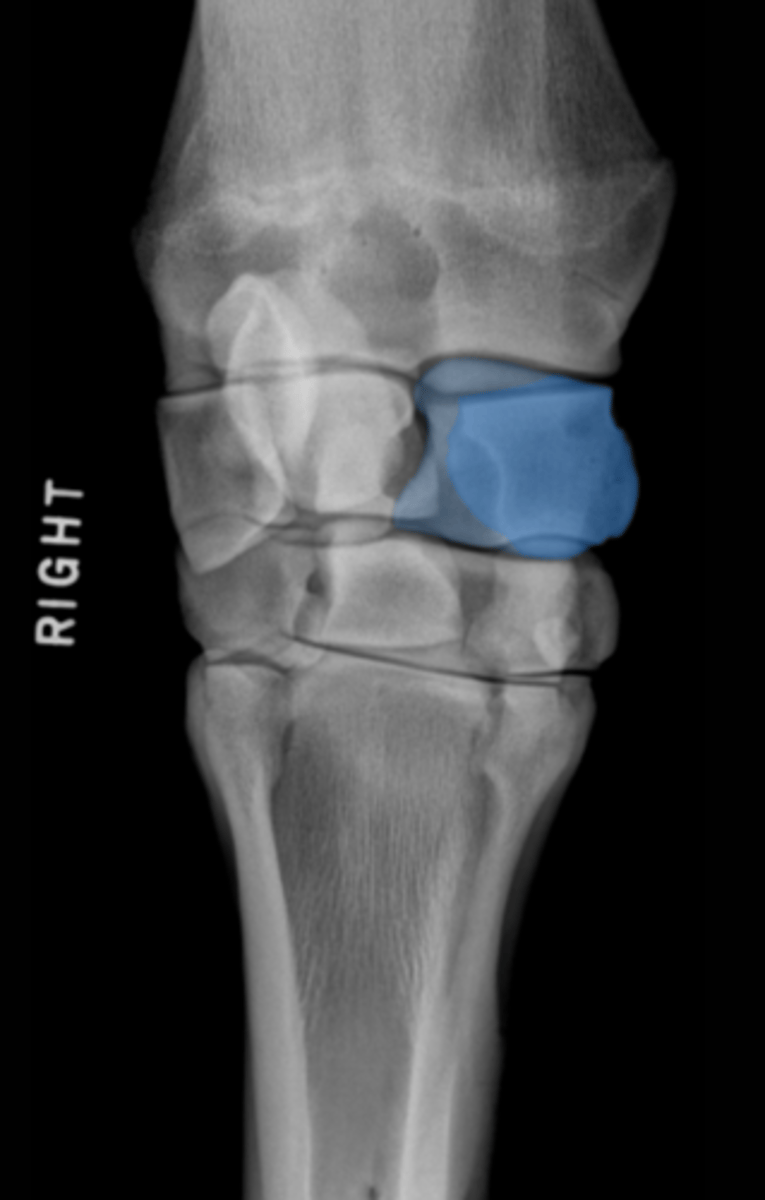

Tarsal I & II

What two bones are highlighted?